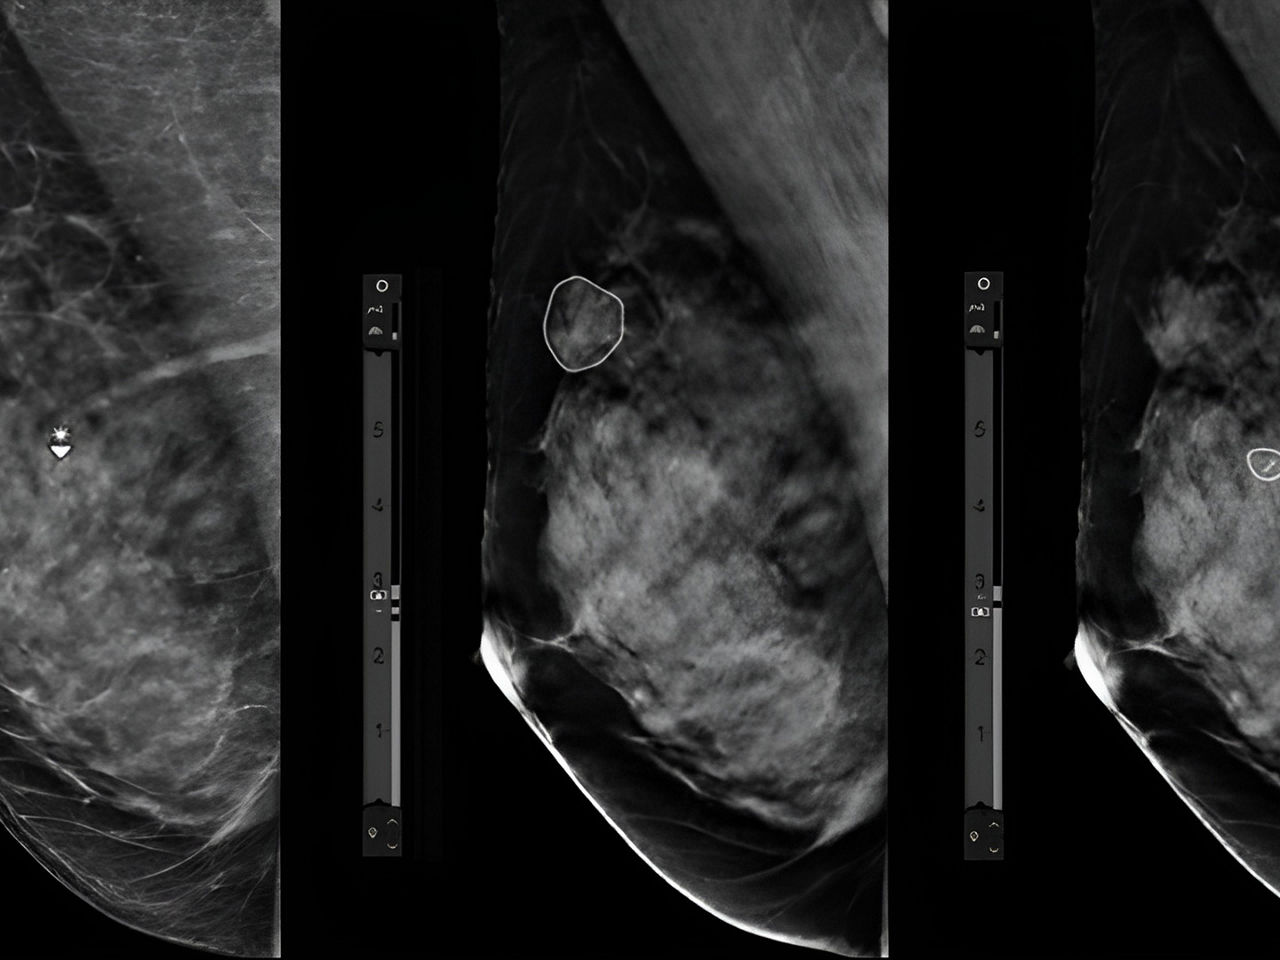

• Concurrent reading, in which AI assists the radiologist in interpreting the images. This technology has the ability to potentially reduce the number of missed breast cancer lesions while helping speed reading time.

To help get us there, we have engineers and data scientists working on our broader platform, preparing for the future. For instance, we’d like breast radiologists and breast surgeons to be able to superimpose mammography, ultrasound, or MRI clinical images on their imaging workstation. Then they could virtually view into a patients’ breast before any invasive procedure to plan the best course of care. That kind of AI goes way beyond imaging and into smarter insights.